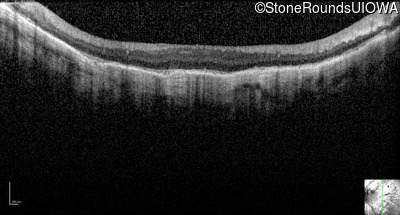

Optical Coherence Tomography - Left - 5/160

Exemplar / OCT Stack